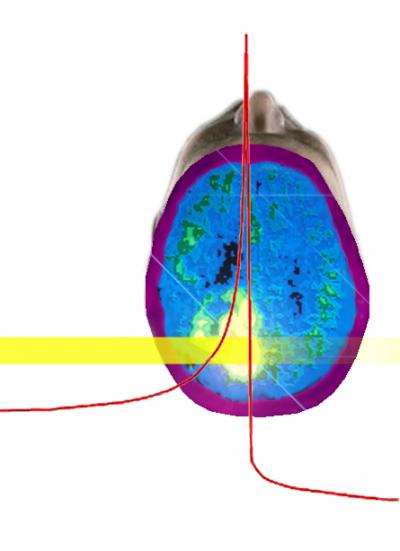

Berkeley Lab's descendant of this imager is called the Compact Compton Imager 2 (CCI-2) and fits on a cart, although Mihailescu says "it still weighs a ton." The ARRA grant is intended to help Mihailescu and Vetter refine a truly compact imager, working with colleagues including I-Yang Lee, who heads the GRETINA gamma-ray tracking collaboration. While it will be useful for security applications and also for basic science, the principal task of the new imager will be to improve the reliability and practicality of cancer therapy using heavy-ion beams.

"DOE has a long interest in cancer therapy with protons and heavy ion beams because of the huge advantage over x-ray therapy," says Vetter. "An ion beam can penetrate deep and deposit most of its energy right in the tumor, with minimal damage to surrounding tissue. But there's a serious drawback. At present there's no way to get a quick measure of the actual dose or how it's distributed."

Ideally, one should be able to make images during treatment, showing exactly where the ion beam is depositing its energy in the tumor. Imaging methods exist, but they take too long: a common therapy uses carbon ions, which react with nuclei in the tissue to create radioactive carbon-11. When carbon-11 decays, it emits positrons and so can be detected by positron-emission tomography, or PET scans.

But carbon-11's half-life is more than 20 minutes, while the cancer treatment lasts only a few minutes. To collect enough data for an accurate dose measure and to find out where the beam actually ends up takes at least half an hour—much too late to obtain an accurate picture of the beam before the activity is diffused or adjust the treatment while underway … or stop it if necessary.

The ion beam excites oxygen and nitrogen as well as carbon when it encounters tissue, and all these excited nuclei instantly emit gamma rays. Here's where the Compton gamma-ray imager comes in.

CCI-2 uses a sandwich of two double-sided germanium detectors and two silicon detectors. By distinguishing a series of events along the path of each scattered gamma-ray photon, the energy, momentum, and angle of the original gamma ray can be calculated; by combining information from enough photons, an image of the source that emitted the gamma rays can be constructed.

Even at its present slow count-rate, CCI-2 can collect and process enough data to construct a 3-D movie of a line source of cesium-137 inside a thin pipe in a room, or a picture that distinguishes two small spheres of tin-113 placed close together. Improved electronics and algorithms, based on those used for the big research detector, GRETINA, will lead to higher resolution and faster response.

"The data used to construct these images allows them to be superposed on visible or x-ray images and viewed from any angle within 360 degrees, ideal for imaging during radiation therapy," Mihailescu says. "And by adding time discrimination, someday we'll be able to correlate the sources with moving objects."